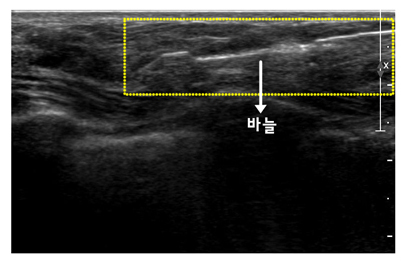

[ 맘모톰 조직검사 ]

[ 맘모톰 조직검사 시술 사진 ]